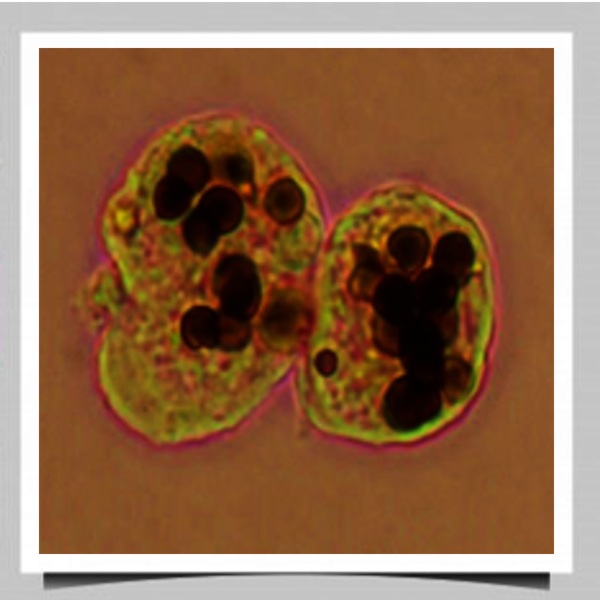

- La patobiología de microorganismos; es decir, estudiamos los procesos y moléculas que algunos agentes patógenos del ser humano emplean como mecanismos de agresión para causar infecciones.Particularmente nuestra investigación se ha enfocado hacia los mecanismos de patogenicidad de los parásitos Entamoeba histolytica (amibas) y Trichomonas vaginalis.

E. histolytica posee una serie de moléculas denominadas factores de virulencia que utiliza para atacar y defenderse del hospedero. Sin embargo, este parásito también posee moléculas que están indirectamente involucradas en el proceso patogénico denominadas determinantes de virulencia que le confieren una alta plasticidad metabólica favoreciendo su adaptación y supervivencia, tales como las esfingomielinasas, GTPasas, etc.

Mecanismos moleculares que regulan la modulación de la virulencia de Entamoeba histolytica

Búsqueda de nuevos factores y determinantes de virulencia de E. histolytica

- Esfingomielinasas: Enzimas multifuncionales implicada en la modulación de la virulencia de E. histolytica.

- GTPasas: Interruptores moleculares implicados en la virulencia amibiana